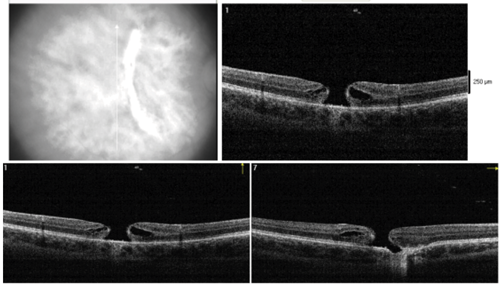

Figure 3: Optical coherence tomography at one month (Top) and three months (Bottom)

after the trauma showing progressive full thickness traumatic macular hole.

The visual prognosis of choroidal rupture has long been thought to be poor when the fovea is involved, with a possible late complication of choroidal neovascularisation. As can be seen from the OCT (Figures 3a and b), the fovea is indeed involved in our patient, still her visual acuity improved remarkably before the macular hole developed. This was first observed by another consultant in my deanery, Mr Raman, who found in a series of 32 eyes that foveal choroidal ruptures may indeed regain good central vision over a longer follow-up period and that multiple choroidal ruptures do not necessarily predict a poor visual outcome [3].